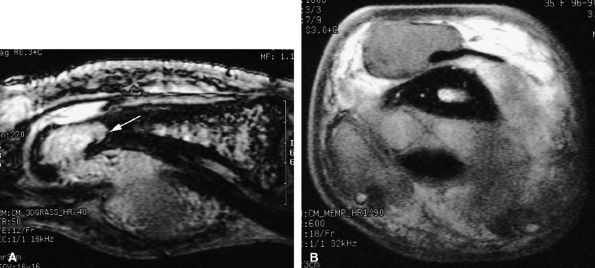

seen with synovial sarcomas. Bone and joint invasion is possible.168 Ultrasonography shows a nonspecific solid mass with a variable color Doppler signal. MR images are specific, depicting a well-defined mass with hemosiderin deposits. Typical signal void artifacts are seen on all sequences, particularly on gradient-echo images, and a more heterogeneous and predominantly low signal is found on T2-weighted images.162,166,169 The lesion typically enhances after intravenous injection of gadolinium (Fig. 11.74). The tendon sheath of the flexor digitorum tendons is usually partially or totally enveloped; the extensor tendons are less commonly involved. Some lesions may be more aggressive, and diffuse lesions are seen in multiple locations with invasion of both the flexor and extensor tendons (Fig. 11.75).170

|

FIGURE 11.74 ● Giant cell tumor of the tendon sheath. Sagittal T2-weighted image (A) and post-contrast T1-weighted image (B) show a palmar mass (arrows) close to the sheath of the flexor tendons with predominant low signal (arrowhead) on the T2-weighted image and strong enhancement following contrast administration.

![]() |

FIGURE 11.75 ● Aggressive giant cell tumor of the tendon sheath. Sagittal post-contrast 3D gradient-echo (A) and axial T1-weighted (B) images depicting a multinodular tumor invading the flexor and extensor tendons as well as the head of the phalanx (arrow).